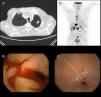

El primer caso corresponde a un hombre de 86 años, exfumador, que ingresó por síndrome general y anemia asintomática. Se identificó en estudios de imagen complementarios (ecografía y tomografía computada [TC] abdominal) afección duodenal inespecífica. Al examen endoscópico se observó que el duodeno presentaba signos de infiltración neoplásica. El análisis histológico reveló que se trataba de un carcinoma pobremente diferenciado no microcítico de origen pulmonar. La TC de tórax evidenció un nódulo espiculado de 15×19×20mm en el lóbulo superior izquierdo sugestivo de tumor primario pulmonar (CAM 5.2 y TTF1 positivos) (fig. 1 A). Dada la edad del paciente, su comorbilidad y su calidad de vida previa en grado 3-4 de la Eastern Cooperative Oncology Group (ECOG) se decidió manejo paliativo, falleciendo a los 4 meses.

A) Imagen de TC en la que se identifica nódulo espiculado en lóbulo superior izquierdo sugestivo de tumoración primaria pulmonar. B) Imagen de cápsula endoscópica con lesiones angiodisplásicas en yeyuno con sangrado activo. C) Imagen de cápsula endoscópica con estenosis yeyunal. D) Imagen de PET en la que se visualiza captación en ganglios mediastínicos y peritoneales sugestivo de diseminación.

El segundo caso es un varón de 68 años, exfumador, con anemia ferropénica grave. El estudio con cápsula endoscópica visualizó lesiones angiodisplásicas en yeyuno con sangrado activo además de una posible estenosis yeyunal (fig. 1B y C). La TC confirmó una neoplasia yeyunal con afectación ganglionar y metástasis hepáticas. Se amplió estudio mediante TC torácica y tomografía por emisión de positrones (PET) confirmando la presencia de enfermedad diseminada con un tumor primario de pulmón (estadioIV). El análisis inmunohistoquímico de las biopsias reveló que se trataba del subtipo adenocarcinoma (CAM 5.2 positivo. CDX-2 y queratina 20 negativos. TTF1 y queratina 7 positivos) (fig. 1D). Dada la buena situación general del paciente se inició quimioterapia (carboplatino [CBDCA] + Alimta + atezolizumab), con buena respuesta (supervivencia a 5 meses desde el diagnóstico).